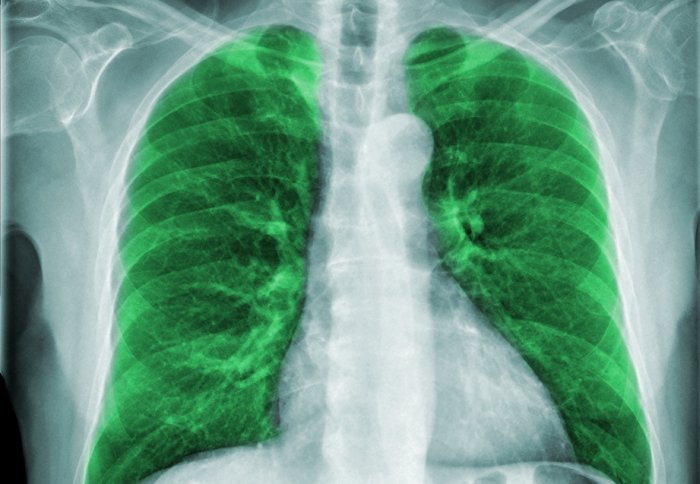

Острая внебольничная пневмония по МКБ-10: признаки и примеры